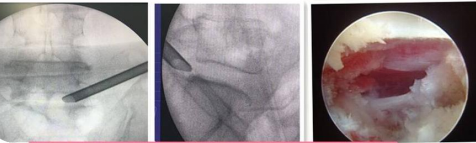

椎間孔鏡技術:

利用椎間孔鏡從患者腰椎側方或者后方進入達到椎間盤突出或者其他病變部位,用專用工具將突出(脫出)的椎間盤組織或病變取出(去除)從而達到治療椎間盤突出或者椎管狹窄的目的。它的優勢在于:局部麻醉、微創、切口小(僅約7mm)出血少,恢復快(第二天即可佩戴硬腰圍下地)及療效好。